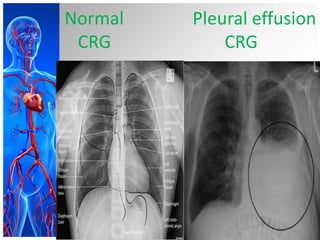

• Chest Radiography :The posteroanterior

and lateral chest radiographs are still the

most important initial tools in diagnosing

a pleural effusion.

Normal

CRG

Pleural effusion